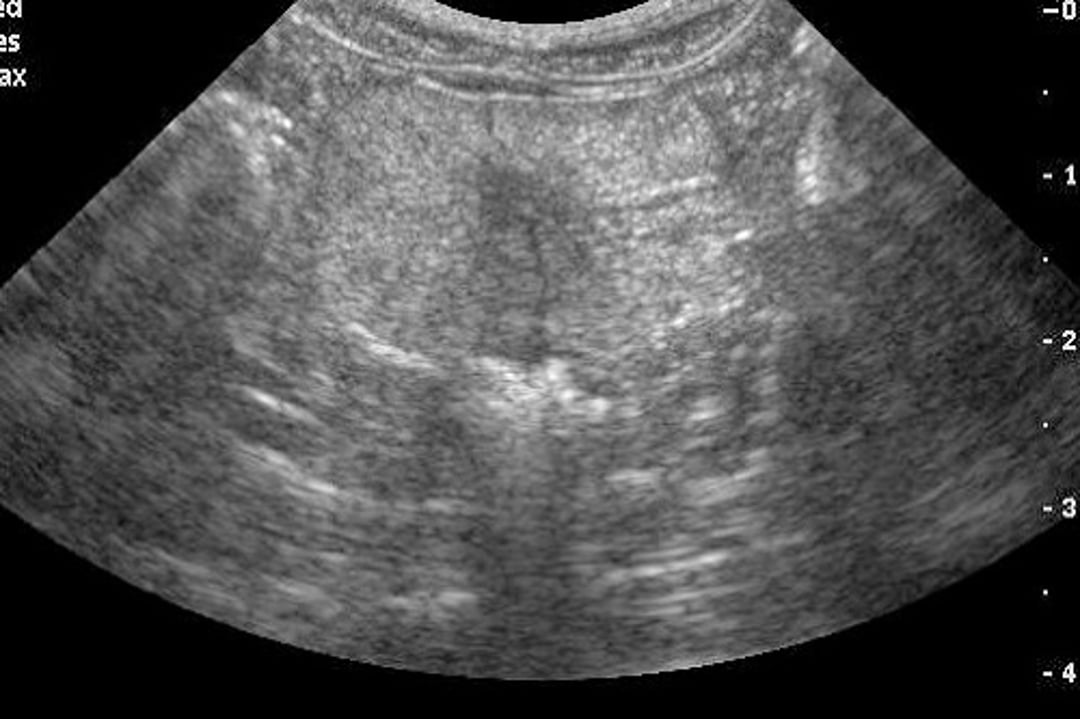

Ecografía transversal de la próstata canina, con cambios típicos de la hiperplasia benigna. Obsérvese las estrías características en el parénquima.

Cortesía de T. W. Baker.